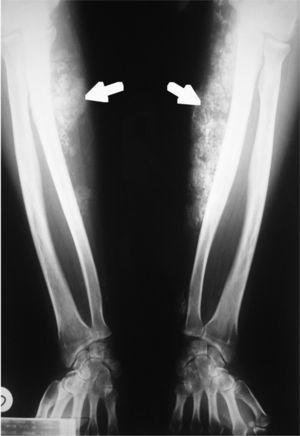

Un subgrupo de pacientes presenta una característica lesión eccematosa en la zona lateral de los dedos de las manos que se denomina “manos de mecánico” (fig. 3) y que se relaciona con la presencia de anticuerpos anti-Jo-1. La paniculitis y la calcinosis (fig. 4) pueden adquirir protagonismo clínico en los pacientes con dermatomiositis, especialmente en su forma juvenil, pero también en el adulto24,25. No es infrecuente apreciar edema con fóvea en las fases agudas de la enfermedad, atribuido exclusivamente al proceso inflamatorio subyacente. La dermatomiositis y la polimiositis se consideran enfermedades sistémicas y como tales presentan las siguientes manifestaciones.